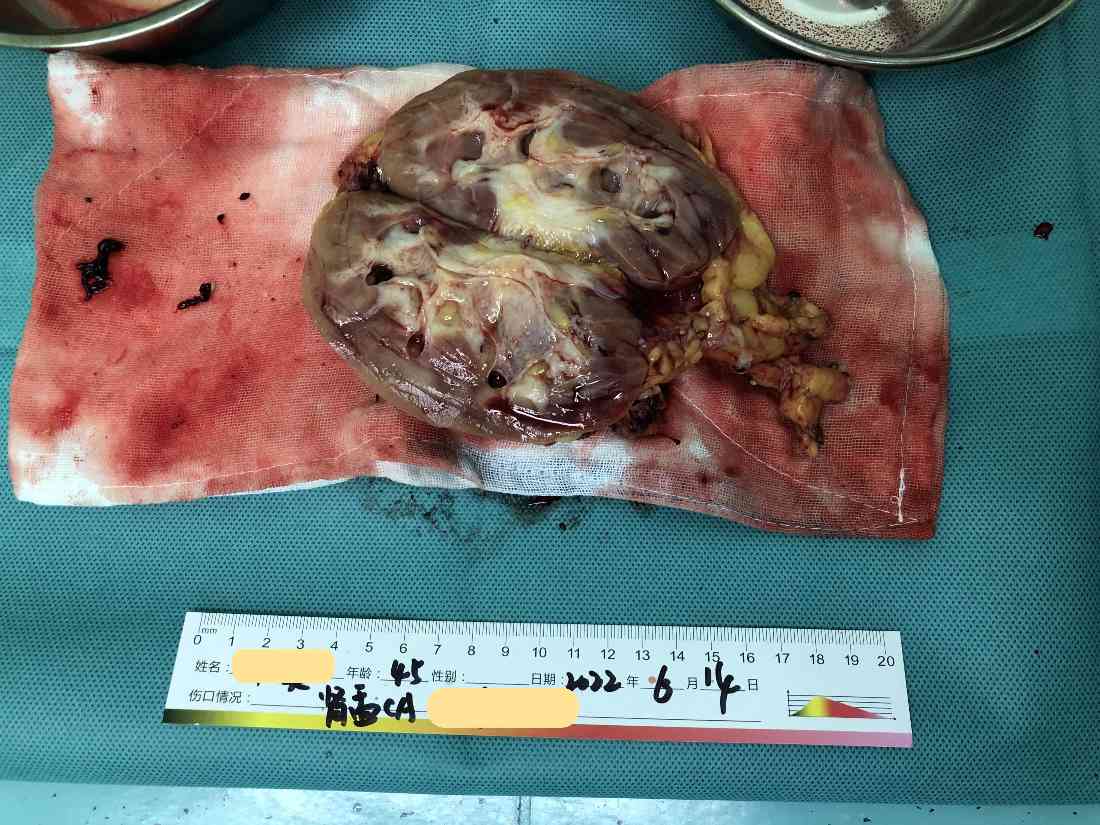

经过充分的术前准备,我们于2022年6月14日为患者进行了手术治疗,术中切除了左侧肾脏、肾上腺、主动脉周围淋巴结、肿瘤侵犯的肌肉和部分腰椎横突;肿瘤侵及的部分主动脉,也进行了部分切除和修补(注:主动脉是人体最大动脉,一般只有心脏和大血管外科医生能进行修补),并在腰椎侵犯处放钛夹标注将来放疗部位。

术后病理: